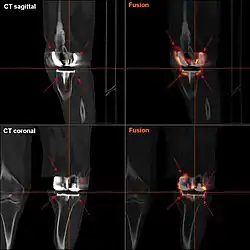

Loosening

Loosening of the prosthesis can be indicated on X-ray by thin radiolucent spaces around the implant, or more obviously by implant displacement.[60]